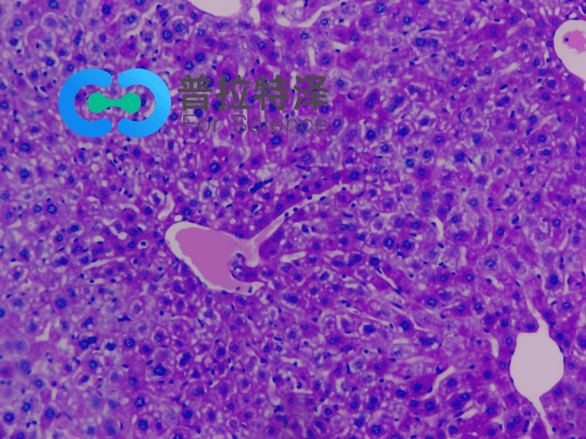

②腎臟疾病診斷

PAS染色在腎臟疾病診斷中同樣發揮著重要作用。對于腎小球腎炎、腎小管間質性腎炎等疾病,PAS染色可以清晰地顯示腎小球基底膜、腎小管及間質等結構的變化,有助于醫生做出準確的診斷。